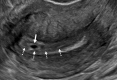

The Society of Radiologists in Ultrasound convened a multisociety panel to develop a first-trimester US lexicon based on scientific evidence, societal guidelines, and expert consensus that would be appropriate for imagers, clinicians, and patients. Through a modified Delphi process with consensus of at least 80%, agreement was reached for preferred terms, synonyms, and terms to avoid. An intrauterine pregnancy (IUP) is defined as a pregnancy implanted in a normal location within the uterus. In contrast, an ectopic pregnancy (EP) is any pregnancy implanted in an abnormal location, whether extrauterine or intrauterine, thus categorizing cesarean scar implantations as EPs. The term pregnancy of unknown location is used in the setting of a pregnant patient without evidence of a definite or probable IUP or EP at transvaginal US. Since cardiac development is a gradual process and cardiac chambers are not fully formed in the first trimester, the term cardiac activity is recommended in lieu of 'heart motion' or 'heartbeat.' The terms 'living' and 'viable' should also be avoided in the first trimester. 'Pregnancy failure' is replaced by early pregnancy loss (EPL). When paired with various modifiers, EPL is used to describe a pregnancy in the first trimester that may or will not progress, is in the process of expulsion, or has either incompletely or completely passed. © RSNA and Elsevier, 2024 Supplemental material is available for this article. This article is a simultaneous joint publication in Radiology and American Journal of Obstetrics & Gynecology. All rights reserved. The articles are identical except for minor stylistic and spelling differences in keeping with each journal's style. Either version may be used in citing this article. See also the editorial by Scoutt and Norton in this issue.